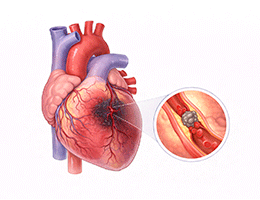

심근경색 (Myocardial Infarction)

협심증 (Angina Pectoris)